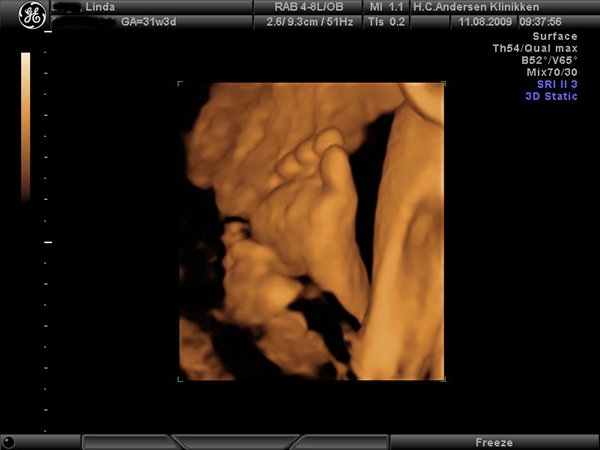

Jeg har lige været til en 3D/4D scanning (27+0), hvilket var en kæmpe oplevelse. Jeg venter en dreng på foreløbig 976 gram

Denne tråd er for alle os som har fået foretaget sådan en scanning. Jeg tænkte det kunne være sjovt at smide nogle fotos op af vores bebzere, da de lå i maven. I profil og forfra.

Skriv gerne hvilken uge scanningen er foretaget, samt evt. hvad køn det er